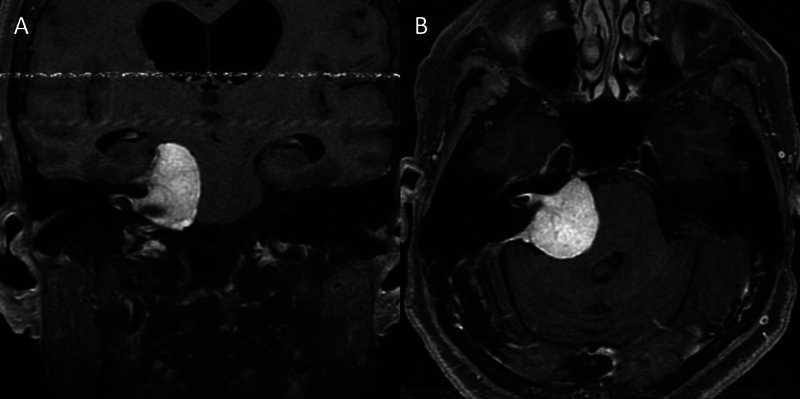

Molecular and Genomic Profiling of Head and Neck Tumors

- PI: Richard V. Smith, MD

- Sponsor: Montefiore Einstein